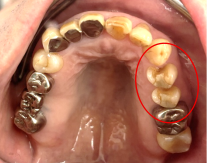

男性 Mさん 50代 (オールセラミック冠)

主訴

右上奥歯が、冷たいものにしみる。

治療内容

歯髄(神経および血管)まで到達する大きな虫歯でしたので、抜髄(歯髄を取り除く)をし、ファイバーコアをいれ、オールセラミック冠を被せました。

所感

現在、保険治療において、限定的ではありますが、大臼歯にも白い被せ物(プラスチック冠)ができるようになりました。しかし、実感としてプラスチック冠は、

- すり減りやすい。割れることがある。

- バイオフィルム(細菌およびそれから産生される副産物の塊)が付着しやすいので、歯周病および2次カリエス(被せ物と自分の歯の境目から再度虫歯になる)になるリスクが高い。

- 変色する。

という点を感じます。白い被せ物が保険の治療でできるという理由で、安易にプラスチック冠を選択し、割れたりすり減ったり、変色したらもう一度被せなおせばいいと考えるのであれば、一度立ち止まって考えてみてください。歯の量は、治療するたびに薄く少なくなり、歯根破折のリスクが高まります。もし大きな虫歯になってしまったら、最高レベルの根管治療をし、最良の被せ物であるオールセラミック冠を被せ、定期的にお口の中のクリーニングをし、同じ歯を2度と治療しないことが、歯を長持ちさせる最良の方法だと考えます。

オールセラミック冠(失活歯):¥104,500(税込)

Before

劣化したプラスチック冠

After